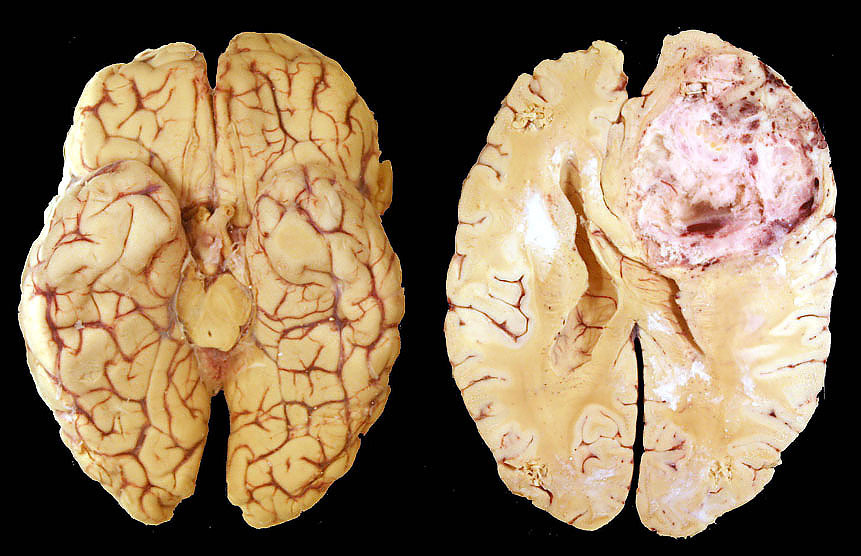

Researchers find new glioblastoma inhibitor

Neuro-oncologists from the University of Alabama at Birmingham and Jiaotong University have found a new treatment that inhibits glioblastoma growth.